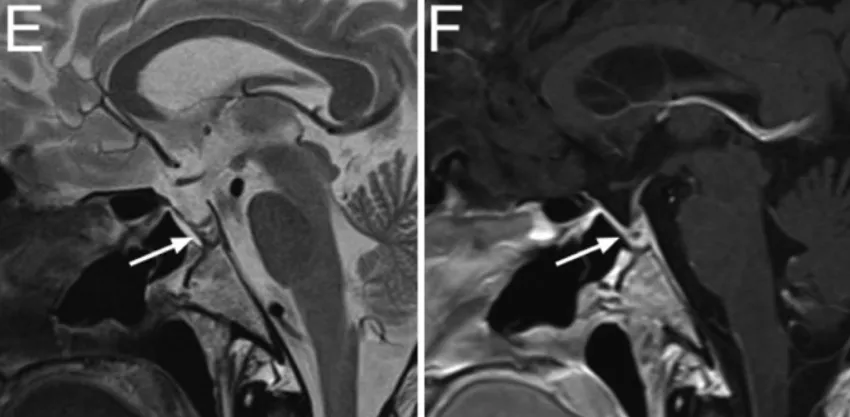

E、F:术后3个月复查矢状位T2WI与T1WI,可见PDS薄膜仍位于原位(箭头)。